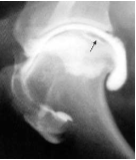

What is wrong with this arthrogram radiograph?

Shoulder: osteochondrosis